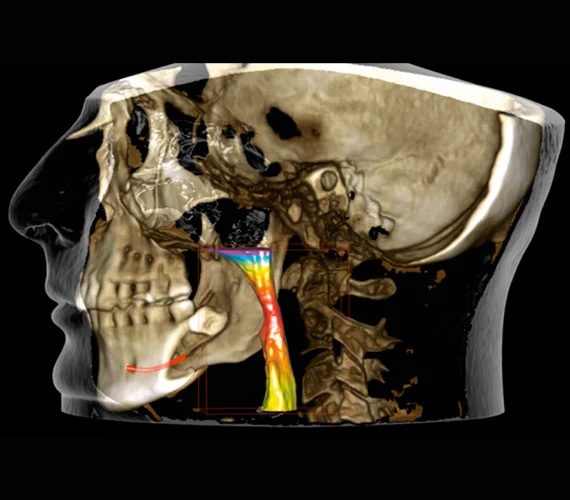

Efektivní analýza dýchacích cest - Segmentace dýchacích cest v softwaru Romexis probíhá pomocí několika jednoduchých kliknutí. Software automaticky vypočítá jejich objem a minimální plochu a vizualizuje dýchací cesty pacienta pomocí výrazných barev. Náš zobrazovací protokol Planmeca Ultra Low Dose™ pro CBCT je zároveň ideální volbou pro vyšetření dýchacích cest, protože výrazně snižuje dávku záření bez statisticky významného snížení kvality diagnostického obrazu.